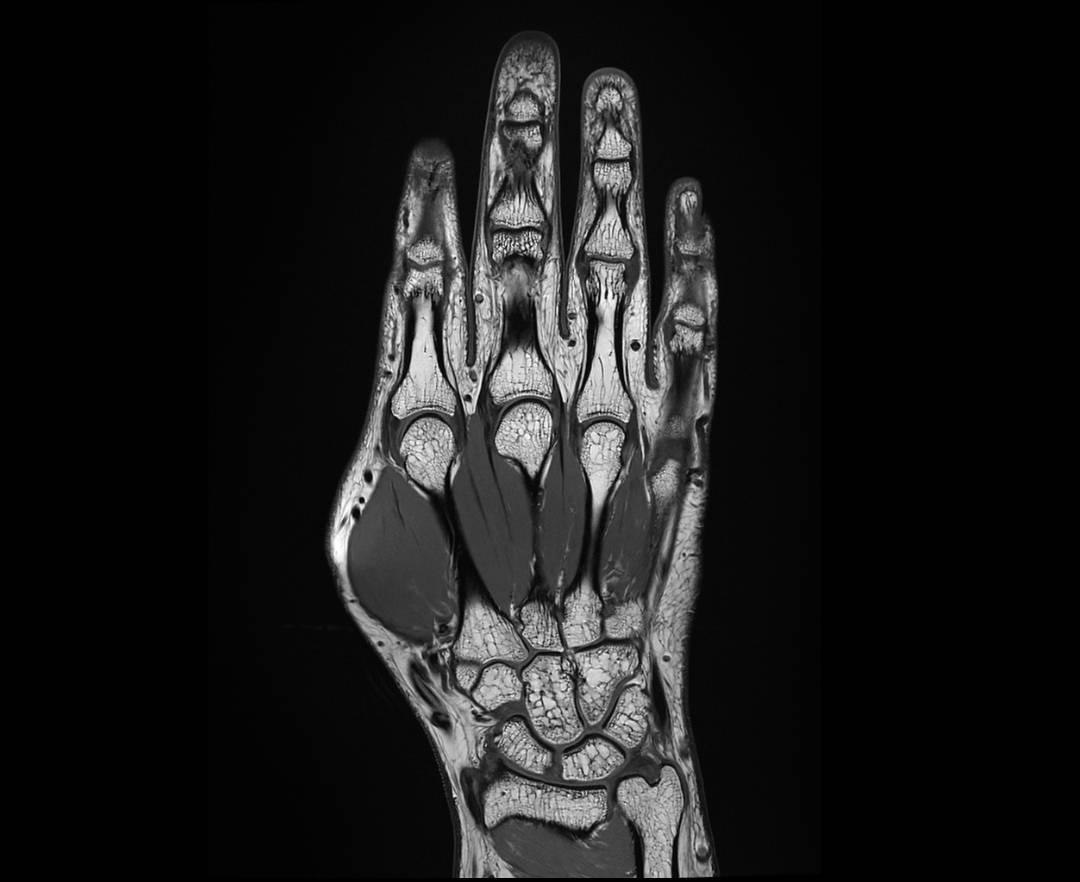

HAND T1 COR